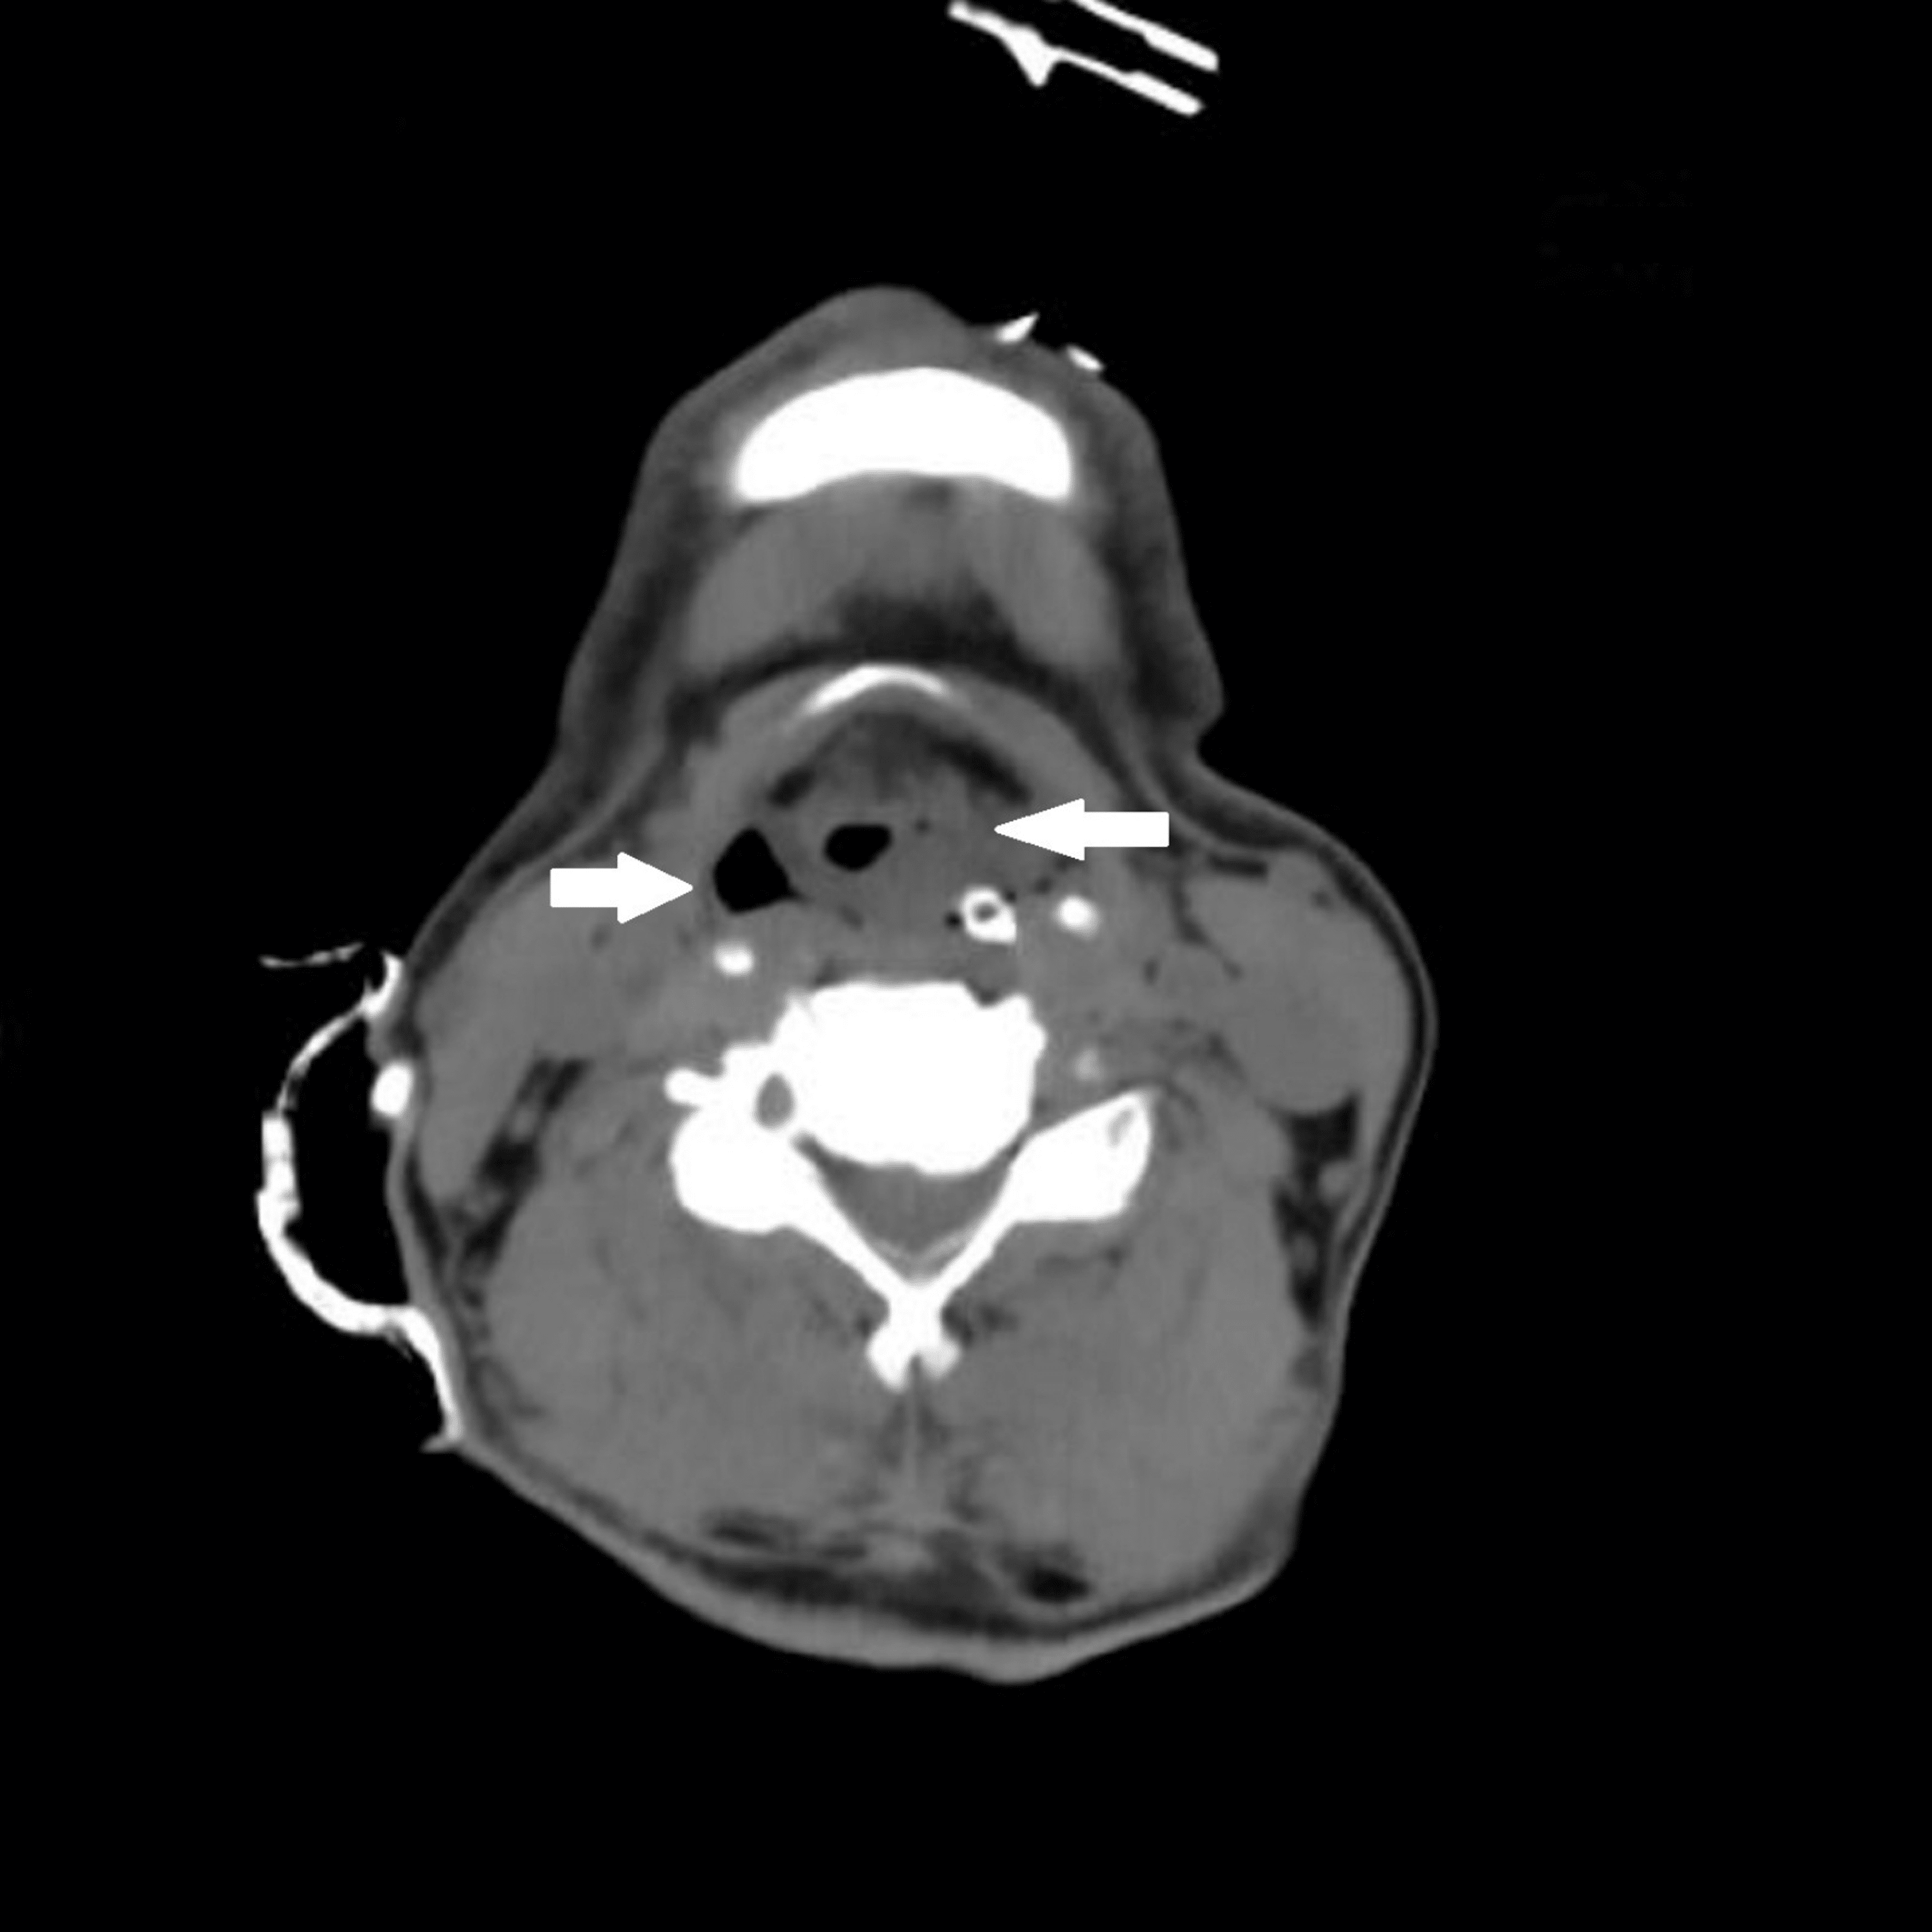

From www.cureus.com

Postextubation Stridor in a Case of Intracranial Bleed Assessing Extubation Airway Edema Consider extubation over an airway exchange catheter: Skill level of junior staff in unit overnight. Laryngeal edema (le) is a frequent complication of intubation and is caused by trauma to the larynx [1, 2]. Can be detected by ‘cuff leak’ test; Leave the airway exchange catheter in place temporarily to ensure that the airway is patent. Post intubation laryngeal edema. Extubation Airway Edema.